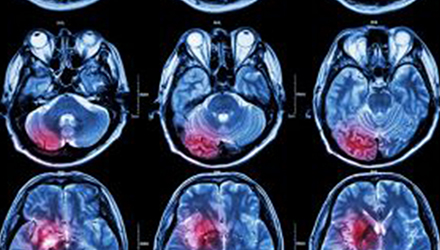

在這項(xiàng)研究中,研究人員使用功能核磁共振成像(fMRI)觀察大腦中血液含氧量的變化。研究人員首先研究了耳鳴患者和無(wú)耳鳴者的大腦活動(dòng),其目的是比較兩組受試者大腦處理情緒的方式。

在功能磁共振成像檢查中,受試者分別聽30種“愉悅”的聲音、30種“不愉快”的聲音和30種“中性”的聲音。這些聲音包括小孩咯咯笑,嬰兒啼哭,以及熱水壺?zé)_的聲音。

功能磁共振成像的結(jié)果顯示,當(dāng)暴露于情緒性聲音下,耳鳴患者大腦不同區(qū)域的活動(dòng)比沒有耳鳴者的活動(dòng)更強(qiáng)烈。接著,研究人員進(jìn)行了更深入的研究:耳鳴患者的大腦活躍性和耳鳴嚴(yán)重程度的關(guān)系。

調(diào)查結(jié)束后,再進(jìn)行功能核磁共振成像檢查。第二輪功能核磁共振成像顯示,那些耳鳴較輕的患者實(shí)際上使用了大腦不同的區(qū)域來處理情緒信息。

傳統(tǒng)觀點(diǎn)認(rèn)為,大腦中的扁桃體是處理情緒的關(guān)鍵,但此次研究發(fā)現(xiàn),那些不被耳鳴困擾的患者實(shí)際上使用更多大腦額葉來處理情緒。這類患者額葉活動(dòng)更顯著的原因是,額葉通常更多地用于注意力、計(jì)劃和沖動(dòng)的控制。